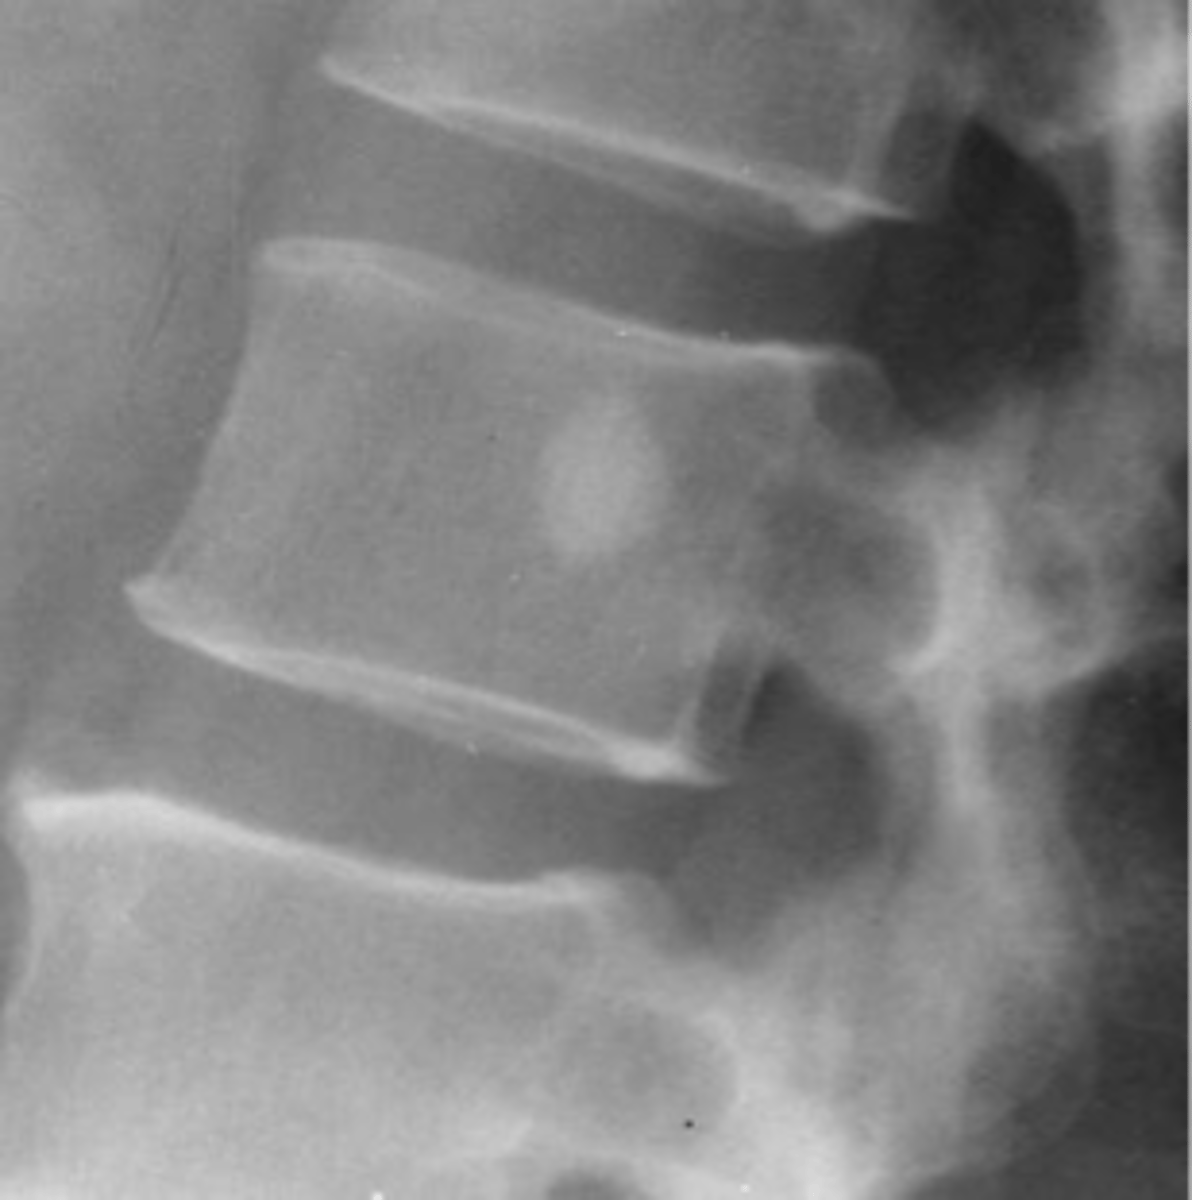

Expansile

_____ vertebral hemangioma

<p>_____ vertebral hemangioma</p>

- Left: Paget Disease

- Middle: Vertebral hemangioma

- Right: Osteoporosis

Complete the DDx for vertebral hemangioma

<p>Complete the DDx for vertebral hemangioma</p>